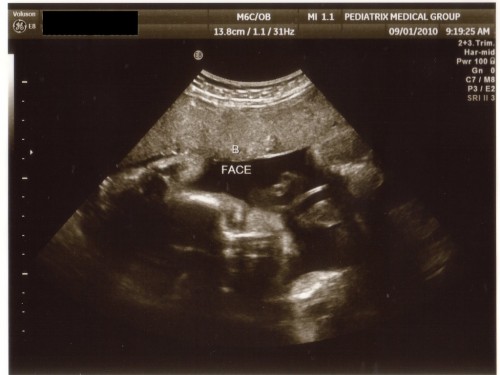

Of course Baby B (Ian) wouldn’t cooperate as well so we couldn’t get a good 4D picture of him. We kind of got a shot of his face but nothing remotely close to what we got on A.

Baby B face